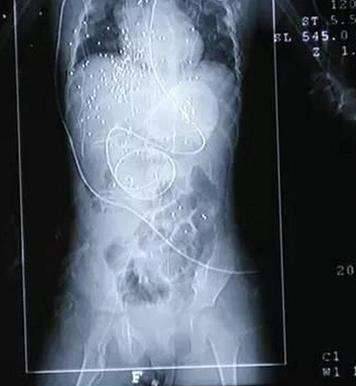

▼经过4个小时的手术后,予希身上的钢珠已取出20多颗,但仍有一百多颗尚未取出来。医师表示予希主要伤到胸腔、腹腔,但心脏、肝脏等器官的表面也有钢珠;由于小如黄豆的钢珠可能在予希体内随血液流动,贸然再做手术可能会造成更大伤害,所以主要先替她进行抗感染治疗,预防併发症及破伤风等。